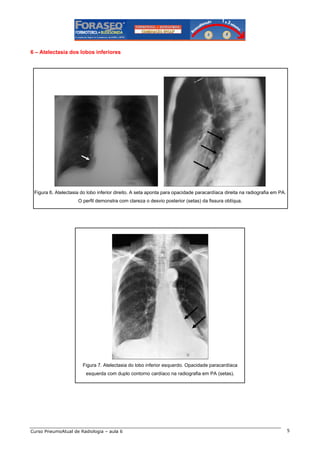

6 – Atelectasia dos lobos inferiores

Figura 6. Atelectasia do lobo inferior direito. A seta aponta para opacidade paracardíaca direita na radiografia em PA.

O perfil demonstra com clareza o desvio posterior (setas) da fissura oblíqua.

Figura 7. Atelectasia do lobo inferior esquerdo. Opacidade paracardíaca

esquerda com duplo contorno cardíaco na radiografia em PA (setas).